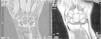

El diagnóstico y la clasificación según estadios de Lichtman fueron realizados con exploración radiológica de las muñecas en proyecciones antero-posteriores y laterales (AP y L). Se confirmó mediante imágenes de RM, en las que aparecía una disminución marcada de la intensidad de la señal con las secuencias T1 (fig. 2).

3 casos en estadios de Lichtman II (esclerosis del semilunar sin colapso) y 3 Lichtman IIIA (colapso semilunar sin rotación escafoides) (figs. 1 y 2)3.

En 4 de los pacientes revisados se realizó RM al año de evolución tras la cirugía, apreciándose en un caso la progresión de la EK de un estadio iiiA de Lichtman a un estadio iiiB, con agravamiento de la fragmentación del Se. No se detectaron aflojamientos del material de síntesis. No se encontraron diferencias reseñables en las RM realizadas en el estudio final actual con respecto a las anteriores.